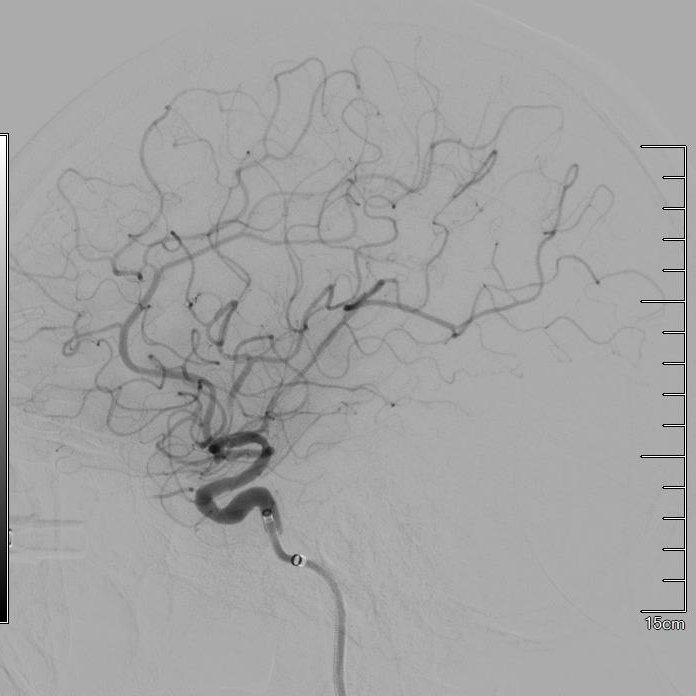

患者术前血管造影证实左侧大脑中动脉M1闭塞